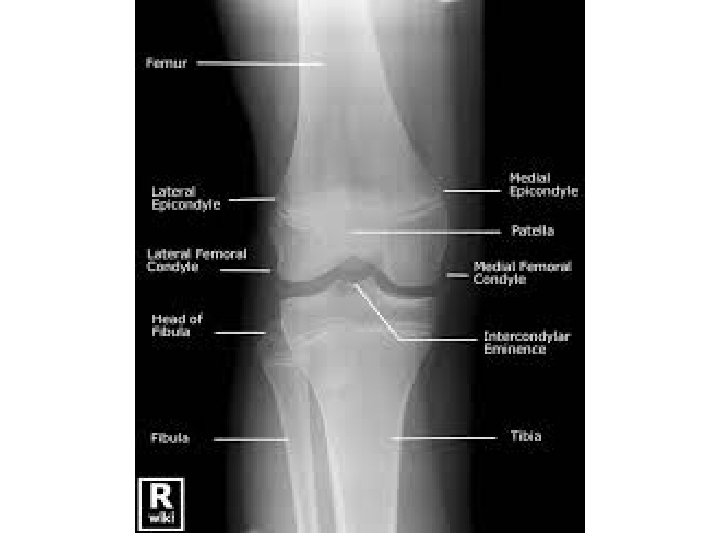

ANATOMI LUTUT TULANG BELAKANG Presentasi dalam acara Seminar Terapi OA dalam praktek sehari-hari Paramedik RS Bethesda Yogyakarta Sabtu, 14 Februari 2015